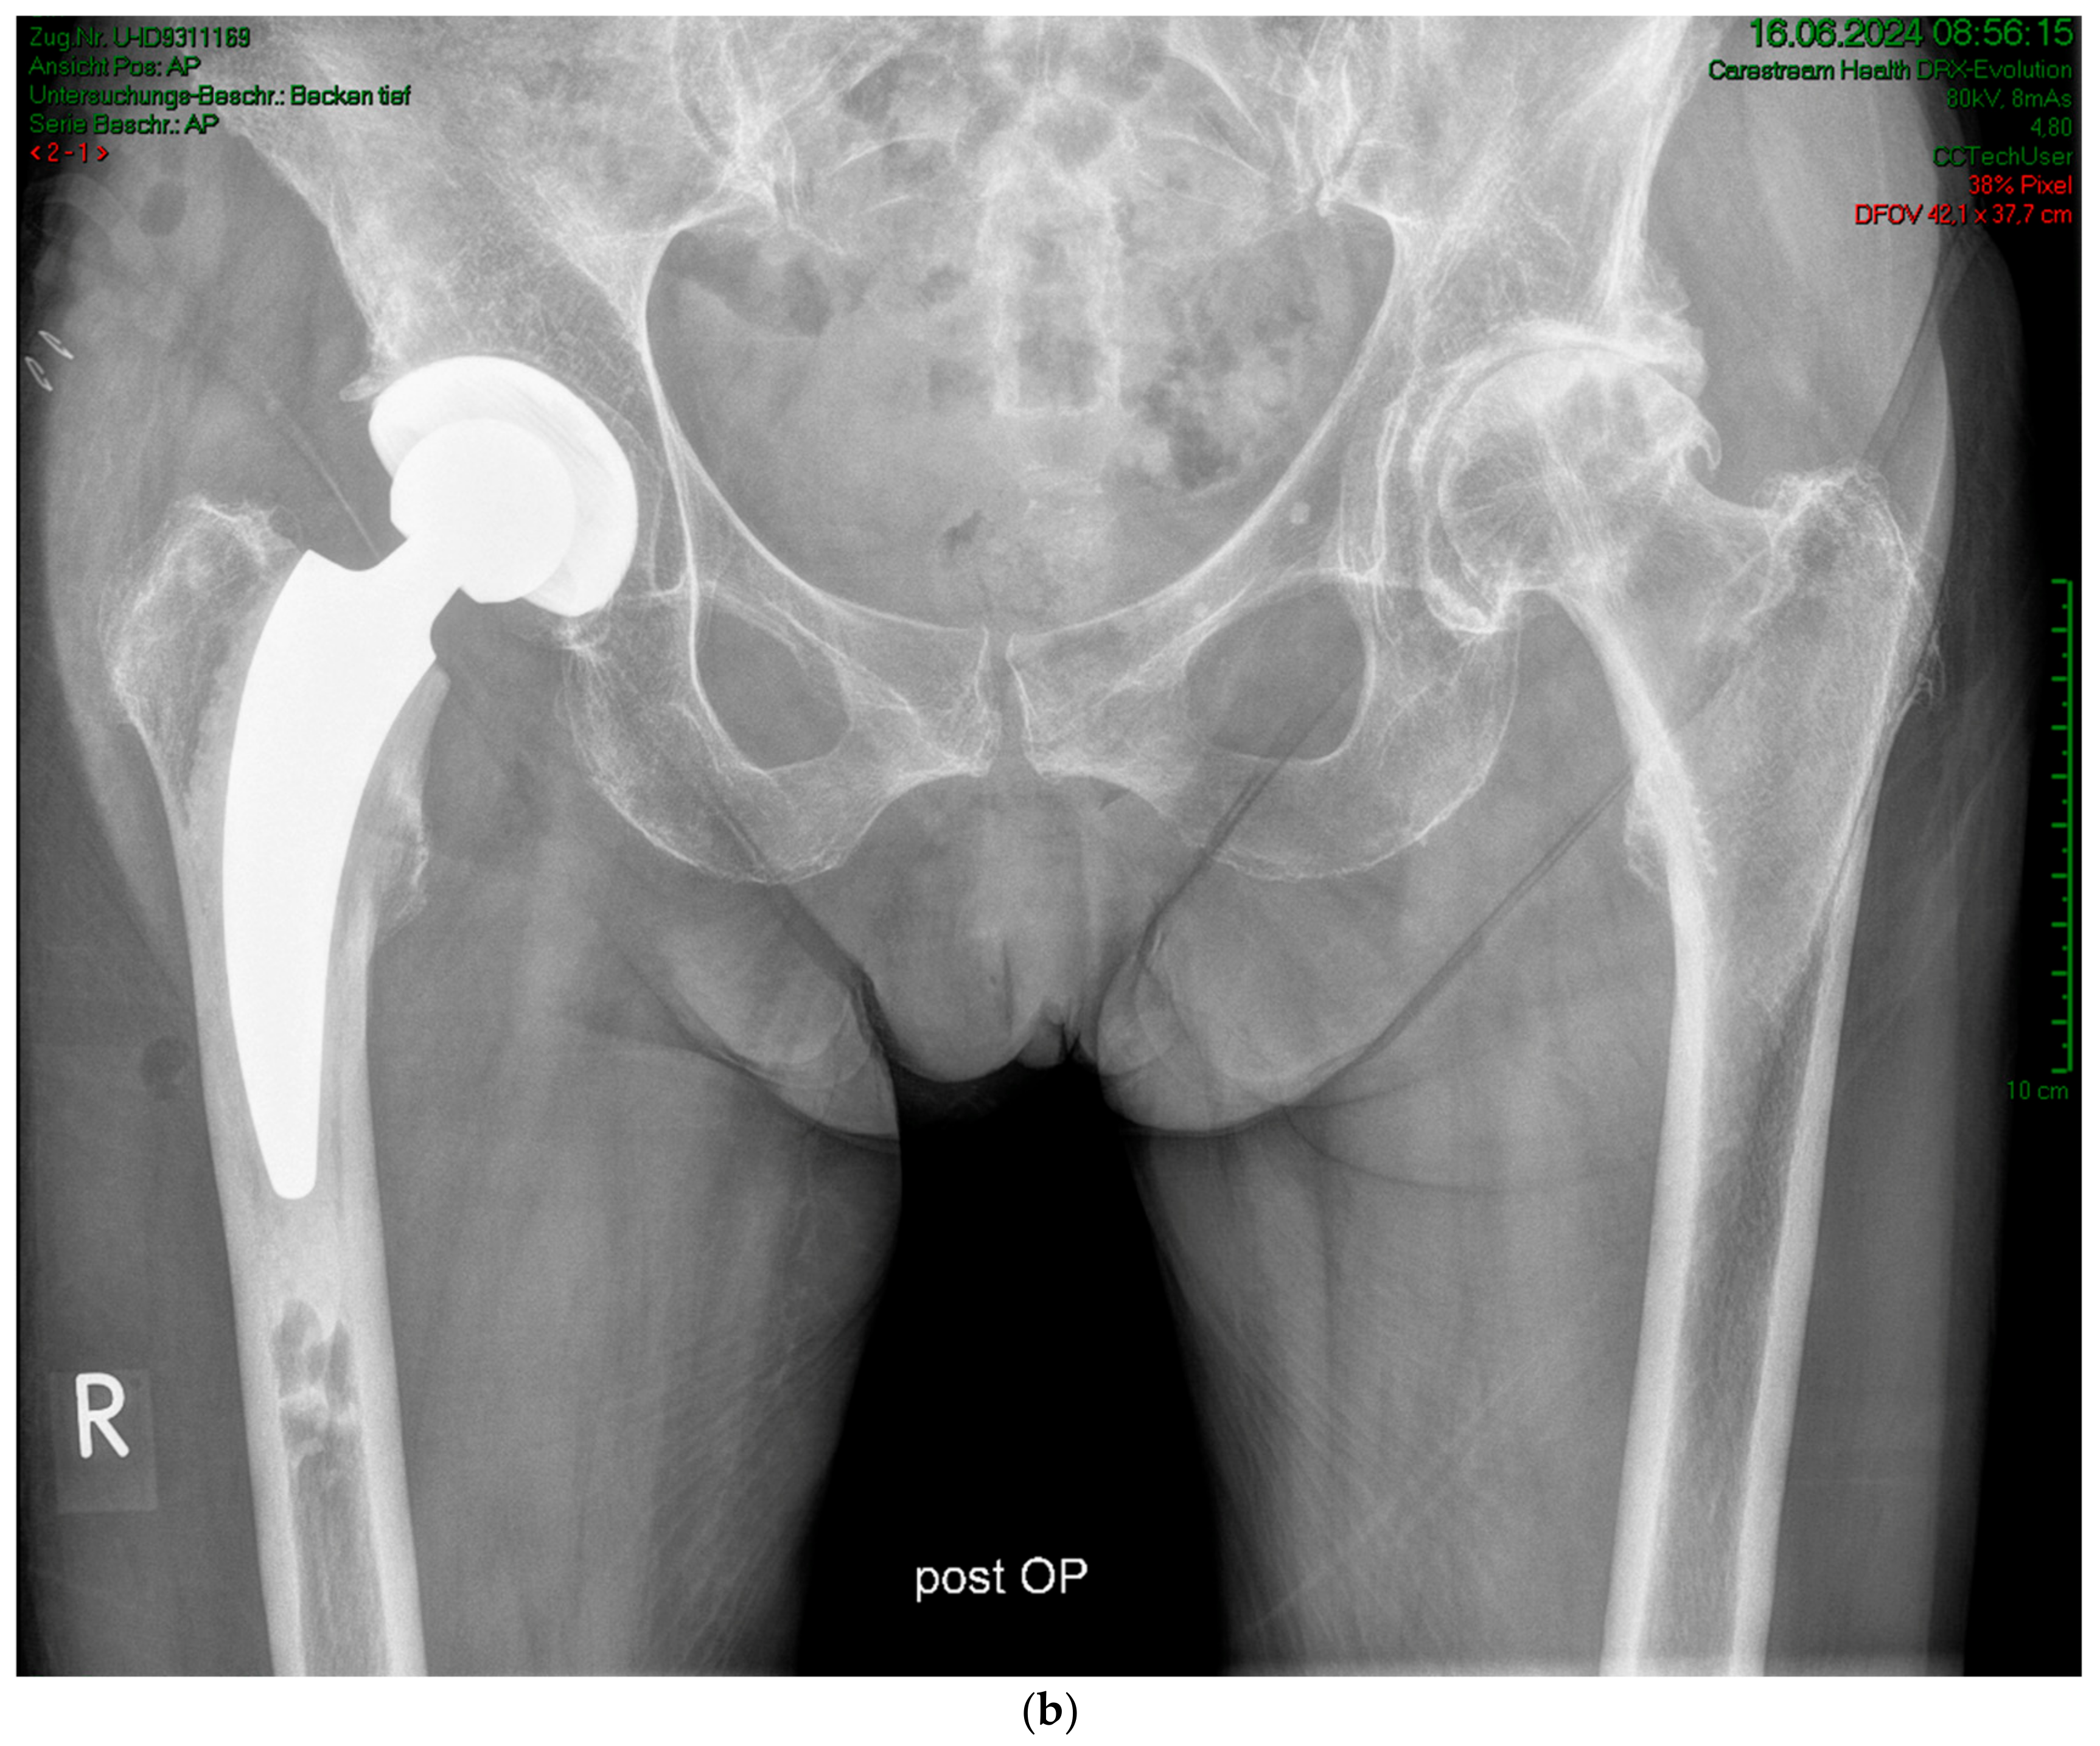

(a) Case #2: Osteoarthritis, female, 85 years old, bilateral sequential implantation of an A2 stem, Dorr B-C femora. (b) Left side: slight distalization of the cement stopper. (c) Right side: no positional change of the cement stopper during the operation.